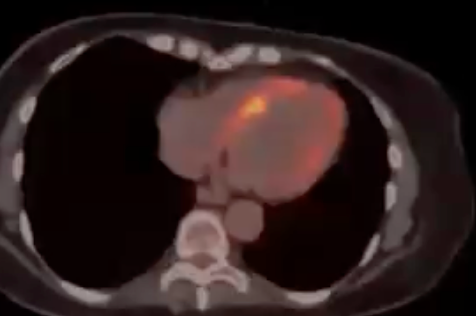

Granulomatous Cardiomyopathy

Cardiac Sarcoid